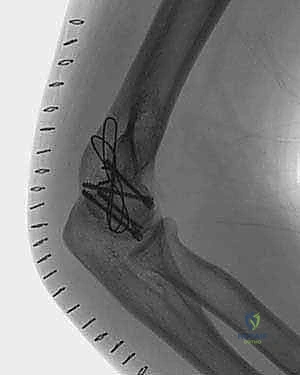

TECH FIG 3 • A. The fracture is reduced and pinned with 0.045-inch K-wires.

> Surgical Warning: If you encounter inability to achieve anatomic reduction, suspect fracture impaction requiring more aggressive disimpaction, or a bone graft may be needed to fill a metaphyseal defect if there's significant bone loss. Do not accept malreduction. - Provisional Fixation: Once reduced, provisionally fix the fragment with 0.045-inch K-wires, typically from anterior-to-posterior. Ensure these K-wires are placed in non-articulating areas or in a path that will not interfere with definitive screw placement.

4. Definitive Internal Fixation:

* **Headless Compression Screws:** These are often preferred for capitellar–trochlear shear fractures due to their ability to be buried below the articular surface and provide strong compression. They can be inserted from either anterior-to-posterior or posterior-to-anterior, depending on the fragment morphology and surgical access.

* **Technique:** Under fluoroscopic guidance, drill a guide wire across the fracture line. Measure, over-drill, tap (if needed), and insert the headless screw. Confirm the screw head is subchondral.

* **AO Cancellous Screws:** If a large subchondral component exists, cancellous screws can be used, typically from posterior-to-anterior. However, remember the increased risk of osteonecrosis with extensive posterior dissection.